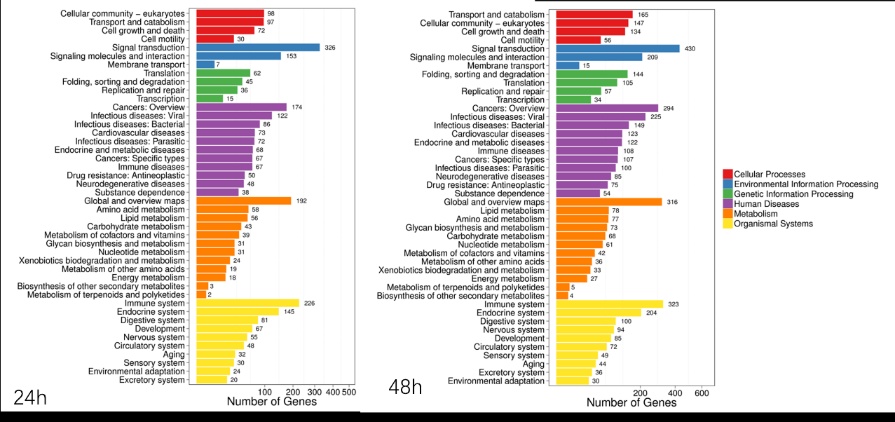

2 结果48 h各组病理结果,对照组脾组织结构正常(见图 1A )。脓毒症组脾组织见白髓结构破坏,红白髓交界模糊,多量组织细胞浸润,红髓充血(见图 1B)。差异mRNA的Volcano-plot分布图(见图 2)。相比于对照组,24 h时脓毒症组脾组织mRNA表达上调的有1 030个,下调的有935个[5];48 h组表达上调的有1 354个,下调的有1 763个。差异mRNA的聚类情况(见图 3)。GO功能分类结果(见图 4)。脓毒症大鼠脾组织部分通路相关基因表达情况(见图 5、6):脓毒症大鼠24 h,48 h脾组织关于细胞因子及其受体相互作用通路相关基因的分布图(见图 7,图 8)。脓毒症大鼠24 h,48 h脾组织关于细胞凋亡相关通路的基因分布图(见图 9,图 10)。

| 图 4 脓毒症大鼠24 h、48 h脾组织mRNA GO功能分类结果 |

早期过度炎症反应、晚期免疫抑制系脓毒症的重要机制之一[6-7]。脾脏为人体免疫器官,在血源性抗原出现时,负责启动免疫反应[9]。脓毒症时SIRS反应可引起脾功能障碍[10]。本研究发现脓毒症48 h大鼠脾组织白髓结构破坏,红白髓交界模糊,其结构改变可能影响其免疫功能。既往对脓毒症大鼠24 h采用基因芯片分析发现部分基因表达异常[11]。若能进一步研究其早晚期的相关基因表达变化也许对脓毒症脾功能障碍有进一步的诠释。本研究采用RNA-seq技术对脓毒症大鼠早晚期脾组织行mRNA检测,是既往研究的深入,发现脓毒症早期组脾组织基因上下调数远少于晚期组,如脓毒症24 h组脾组织mRNA上调数1 030个,下调数935个,而48 h组mRNA上调数1 354个,下调数1 763个,差异明显(见图 2),符合疾病的发展过程。从图 3看,脓毒症24 h、48 h部分区域从红色趋于变浅甚至变蓝,浅蓝趋于蓝色,直观的反应脓毒症时脾脏基因表达量变化情况。从GO功能分类结果(图 4)得知,cellular processes、Environmental informationProcessing、Genetic Information Processing、Human Diseases、Metabolism、Organismal Systems相关功能基因随时间发展出现差异表达数为上升趋势。进而我们对其分析发现,脓毒症早晚期脾mRNA出现变化主要涉及细胞因子与其受体相互作用、IL-17、T细胞受体、TH1、TH2细胞分化、TNF、Toll受体、凋亡等相关信号通路。研究显示,脓毒症晚期免疫抑制可能是脓毒症患者死亡的主要原因,免疫治疗可能是未来一大趋势[12-15]。本文拟从炎症反应与细胞凋亡相关通路来阐述脓毒症脾功能障碍的相关机制。